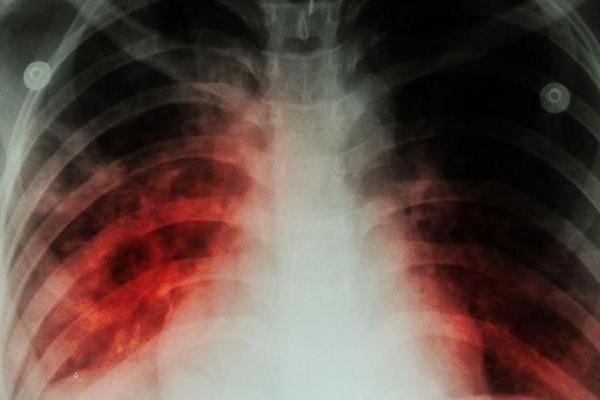

Ilustrasi - infeksi paru-paru (Foto: Berita Kesehatan)